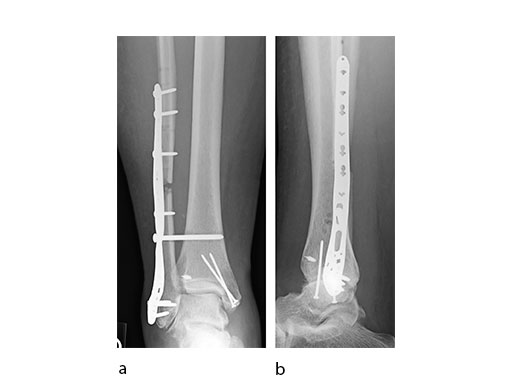

Case 3: Horse fall (Case provided by Mark Lee, Sacramento, USA)

A 45-year-old patient fell from his horse, receiving a closed bimalleolar fracture/ dislocation (Fig 10). Computed tomorgraphy demonstrated an additional anterolateral avulsion injury and syndesmosis dislocation. Osteosynthesis was conducted with a VA-LCP Lateral Distal Fibula Plate.

Push technique was required to achieve fibular reduction, and the syndesmosis was reduced and clamped with periarticular clamps (Fig 11). Postoperative x-rays at 4 weeks demonstrated good maintenance of reduction (Fig 12).